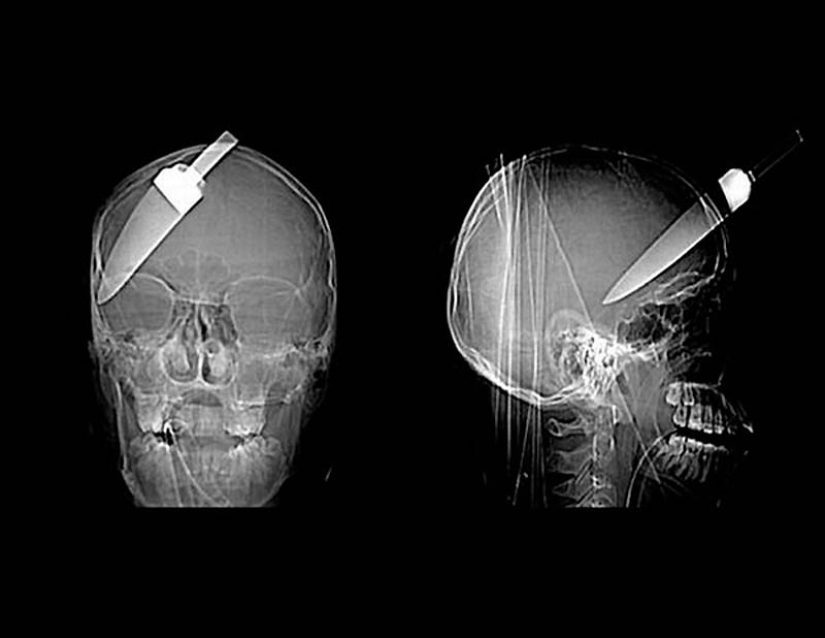

13. Clavo en el cráneo humano: el paciente se disparó accidentalmente con un martillo neumático. Ni siquiera se dio cuenta de que se había disparado a sí mismo – un clavo de 10 cm de largo fue encontrado solo después de 6 días.

15. Un cuchillo en la cabeza de un niño de 10 años. El chico sobrevivió.

18. un cuchillo de 12 centímetros en el cráneo de un adolescente.